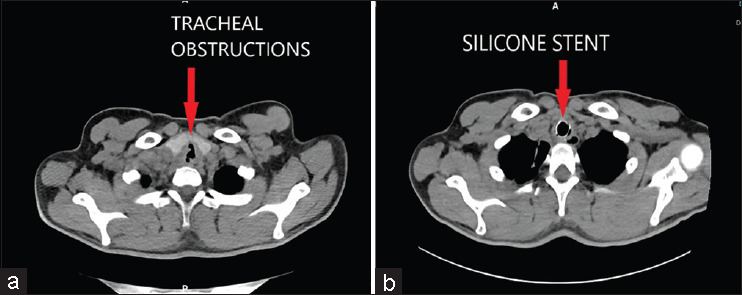

We present a case of tracheal necrosis due to mucormycosis in a young diabetic male. He presented with stridor due to airway obstruction from the necrosed tracheal wall. We used a silicon tracheal stent to maintain airway patency and support the airway. This case highlights the use of tracheal stenting to stabilize the airway in an extremely necrosed and friable trachea, which is not fit for surgical resection due to the involvement of the long segment of the trachea. To the best of our knowledge, the use of stents to stabilize necrosed tracheal walls in cases of mucormycosis has not been reported so far.